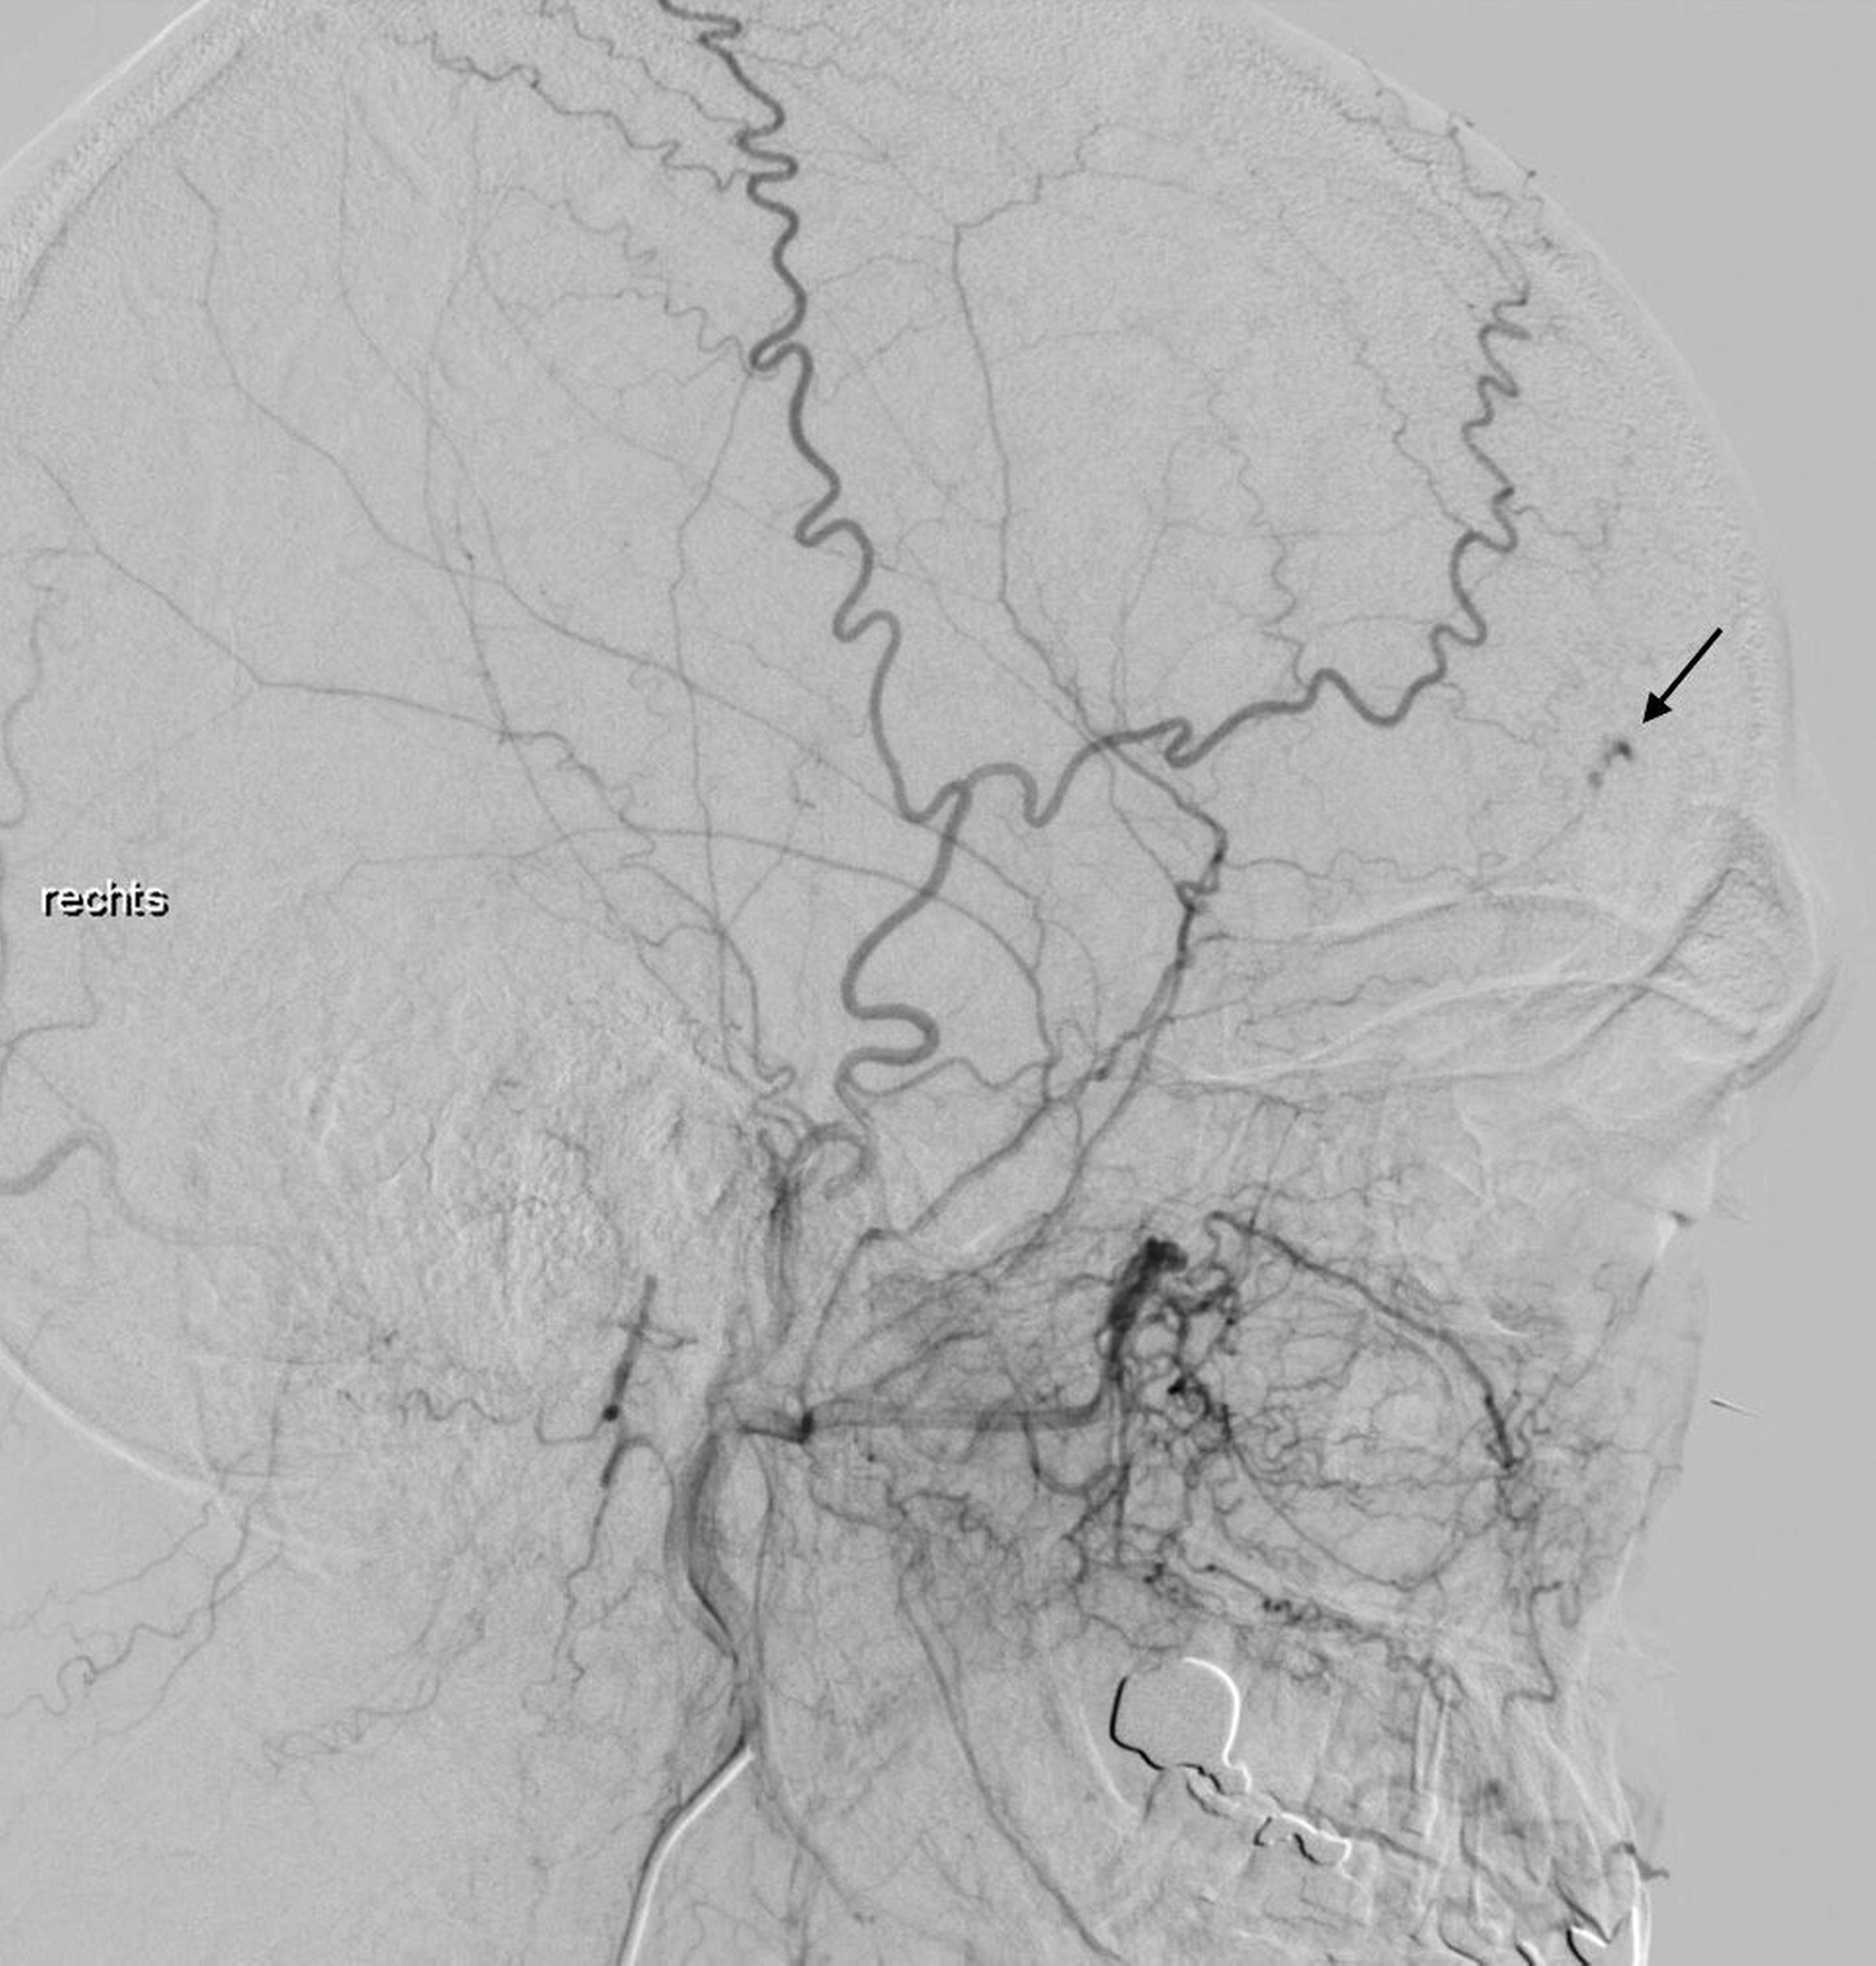

Die anschließend aufgrund der Verdachtsdiagnose durchgeführte Digitale Subtraktionsangiografie (DSA) zeigte einen fokalen Nidus unklarer Entität, der arteriell hauptsächlich über das Stromgebiet der A. carotis externa gespeist wurde (Abbildungen 5 und 6). Nach Vorstellung in einer interdisziplinären Fallkonferenz des Kopf-Hals-Zentrums wurde eine Resektion der Raumforderung über einen bikoronaren Zugang in einer kombiniert mund-, kiefer-, gesichtschirurgisch-neurochirurgischen Operation durchgeführt.

Die knöcherne Defektdeckung erfolgte mit einem Tabula-externa-Transplantat, das vom Os parietale entnommen und mit einer Miniplattenosteosynthese fixiert wurde. Das histomorphologische Bild war am ehesten mit einem kavernösen Hämangiom vereinbar. Die Möglichkeit einer endovaskulären Therapie (zum Beispiel Coiling) war aus radiologischer Sicht nicht gegeben.

Ein weiterer Vorteil einer chirurgischen Entfernung des Befunds ist, dass nur so eine vollständige histopathologische Aufarbeitung und damit die Sicherung der Verdachtsdiagnose erfolgen kann. Ein kombiniert interventionell-chirurgisches Vorgehen mit präoperativem Verschluss eines zuführenden Gefäßes kann bei „high-flow“-Läsionen die perioperative Blutungsgefahr signifikant mindern [Isaac et al., 2018; Konior et al., 1999].